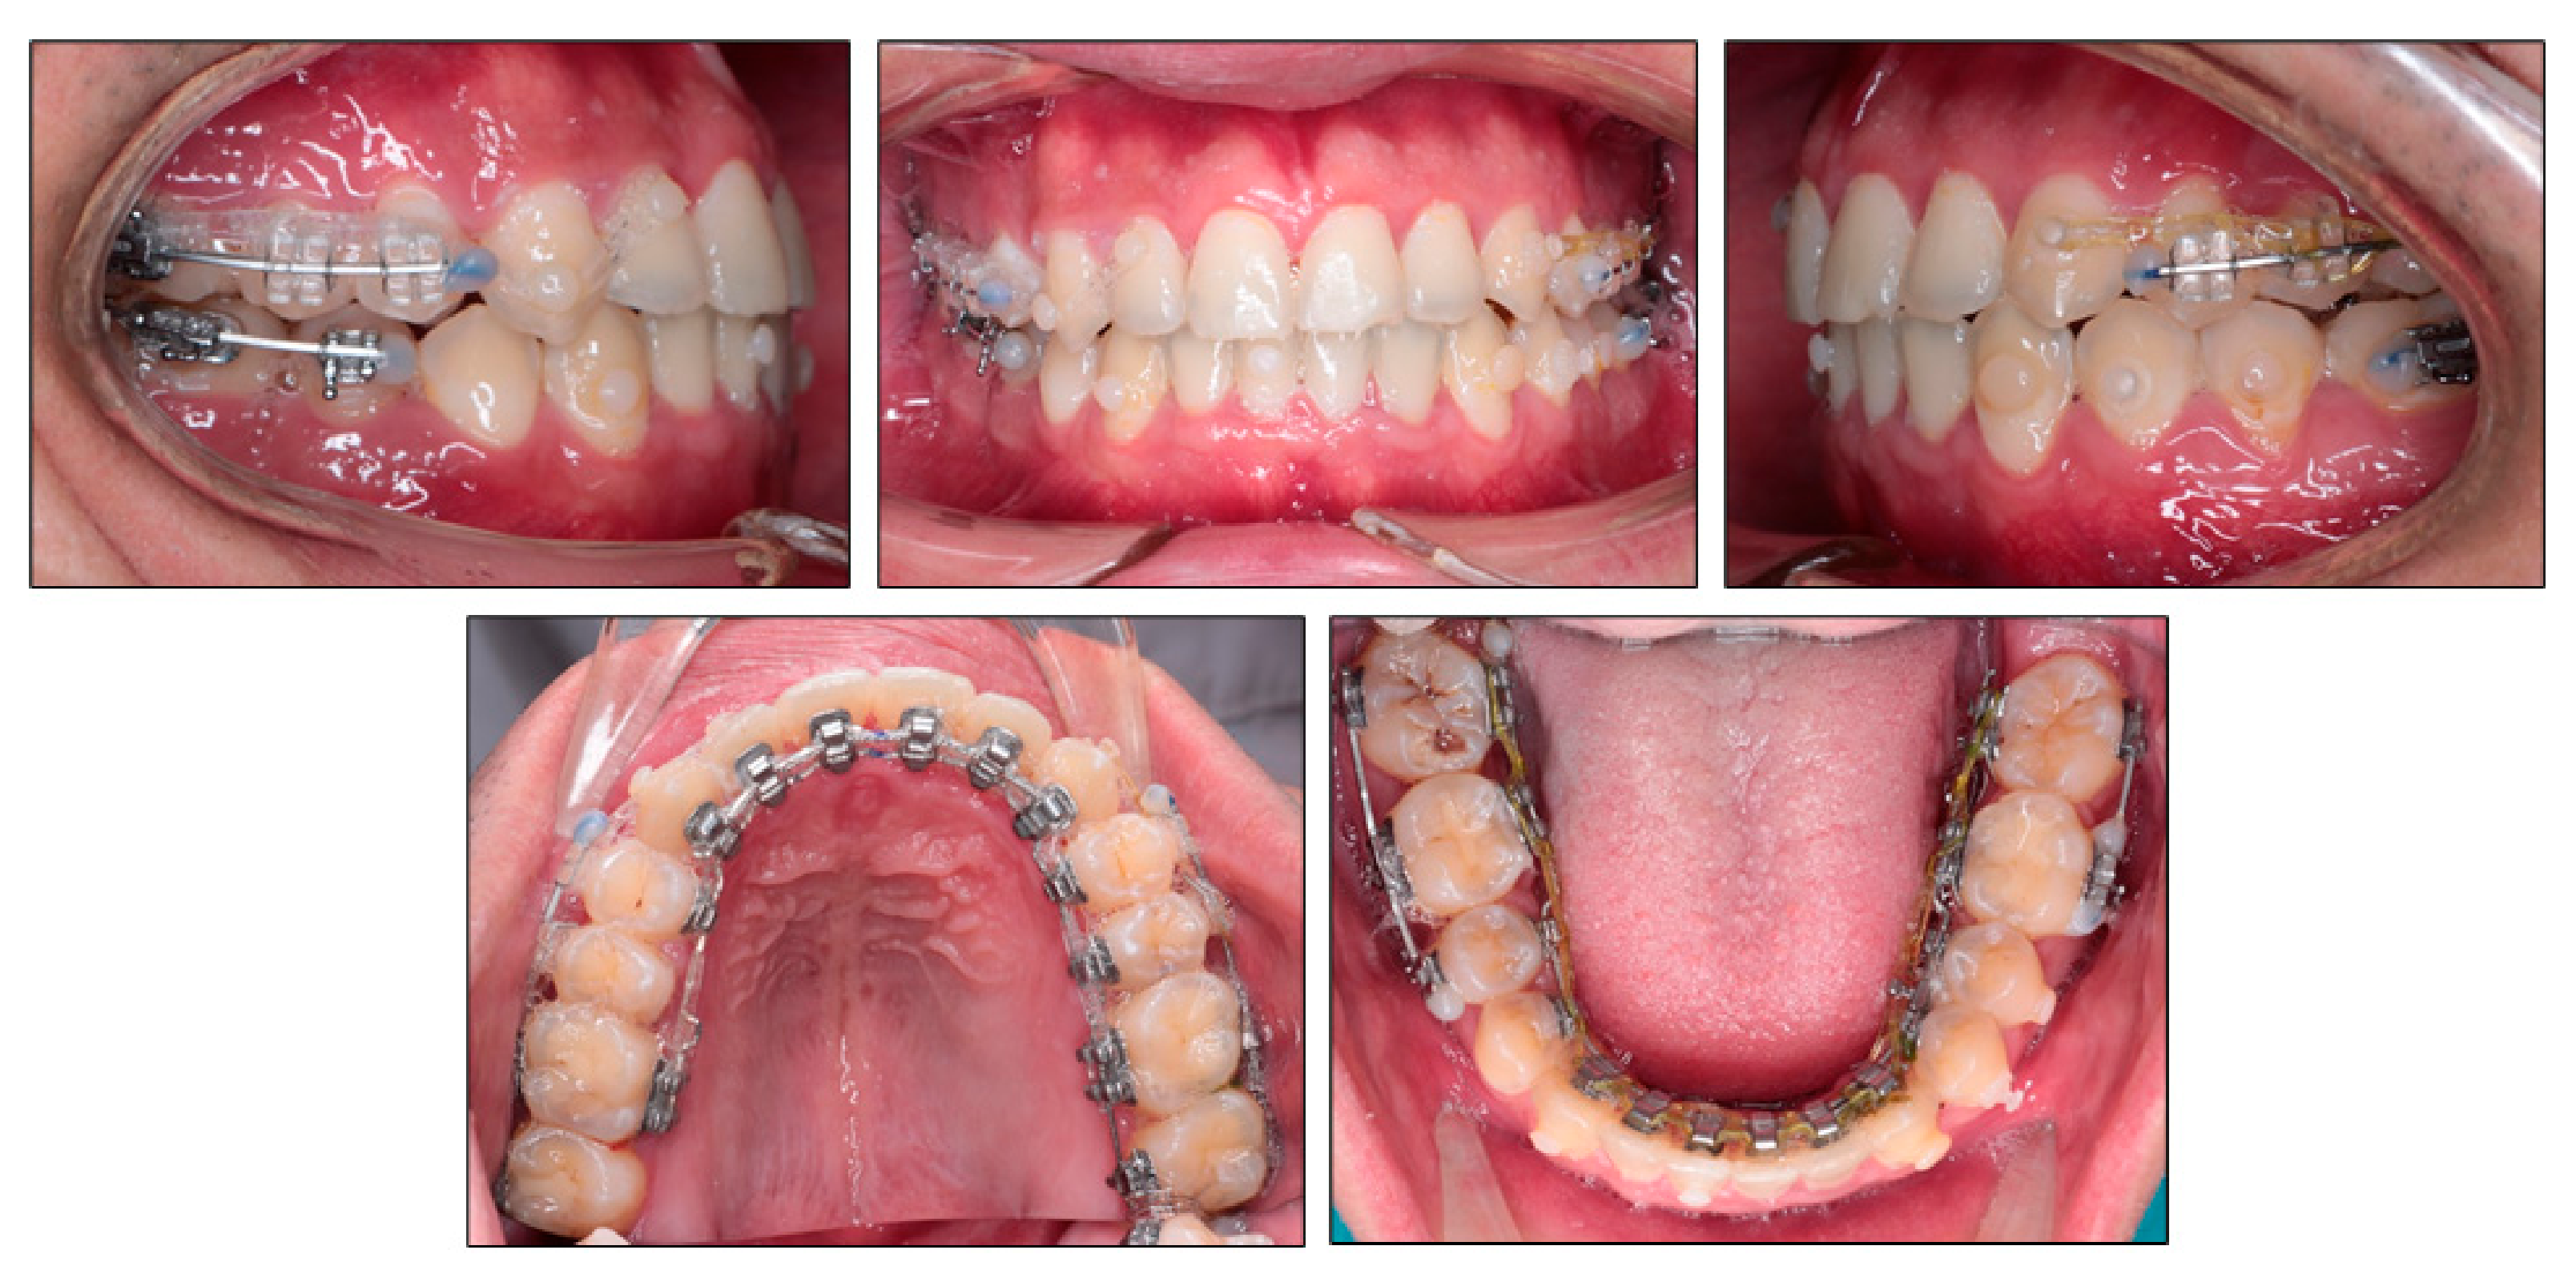

2.5. Treatment Progress

3. Results